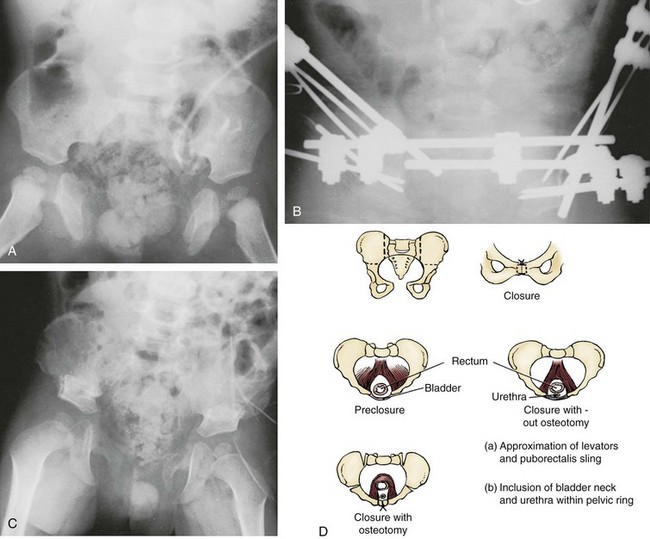

Pelvic osteotomy performed at the time of initial closure confers several advantages including (1) easy approximation of the symphysis with diminished tension on the abdominal wall closure and elimination of the need for fascial flaps; (2) placement of the posterior vesicourethral unit deep within the pelvic ring, enhancing bladder outlet resistance; and (3) bringing the large pelvic floor muscles near the midline, where they can support the bladder neck and aid in eventual urinary control (Fig. 124–17). After pubic approximation with osteotomy, some patients show the ability to stop and start the urinary stream, experience dry intervals, and in some cases become completely continent (Gearhart and Jeffs, 1991a). In a review of a large number of patients referred to our institution after failed exstrophy procedures, it was found that a majority of the patients who had partial or complete dehiscence of the bladder or major bladder prolapse had not undergone a prior osteotomy at the time of initial bladder closure (Gearhart et al, 1993b). The authors recommend performing bilateral transverse innominate and vertical iliac osteotomy when bladder closure is performed after 72 hours of age (Fig. 124–18). In addition, if the pelvis is not malleable or if the pubic bones are more than 4 cm apart at the time of initial examination under anesthesia, osteotomy should be performed, even if closure is done before 72 hours of age. A well-coordinated surgery and anesthesia team can perform osteotomy and proceed to bladder closure without undue loss of blood or risk of prolonged anesthesia in the child. However, it must be realized that osteotomy together with posterior urethral and bladder closure and abdominal wall closure is a 5- to 7-hour procedure in these infants.

Figure 124–17 A, Eight-month-old patient with classic bladder exstrophy closed at birth without osteotomy with complete dehiscence. Patient was initially seen at 8 months of age. B, Patient after having undergone anterior innominate and vertical iliac osteotomy and placement of intrafragmentary pins and external fixator. C, The same patient 4 months after removal of external fixator and pins. Successful closure was achieved. D, The technique of combined osteotomy showing incision sites.

The most frequently used osteotomy today is the bilateral anterior innominate and vertical iliac osteotomy, popularized by Gearhart, Sponseller, and colleagues in 1996 (Gearhart et al, 1996b). This approach improves the ease of symphyseal approximation in the patient with exstrophy compared with posterior approaches, which require turning the patient. In our experience, this osteotomy is superior to the pubic mobilization seen with simple bilateral transverse anterior innominate osteotomy or even pubic ramotomy. With the ease of approximation obtained with this combined osteotomy, tension on the midline abdominal closure is lessened and the rates of bladder dehiscence and bladder prolapse are markedly decreased (Gearhart and Jeffs, 1998). In addition, pelvic closure allows approximation of the levator ani to strengthen the puborectalis sling, with positioning of the bladder neck and posterior urethra deep within the pelvic ring and improved continence rates. Besides the ease of approximation, combined osteotomy was developed for three reasons: (1) Osteotomy is performed with the patient in the supine position, as is the urologic repair, thereby avoiding the need to turn the patient; (2) the anterior approach to this osteotomy allows placement of an external fixator device and intrafragmentary pins under direct vision; and (3) the cosmetic appearance of this osteotomy is superior to that of the posterior iliac approach (Gearhart et al, 1996b).

Whichever type of osteotomy is used, pelvic ring closure not only allows midline approximation of the abdominal wall structures but also allows the levator ani and puborectalis muscles to lend potential support to the bladder outlet, thus increasing resistance to urinary outflow (see Fig. 124–17D) (Sponseller et al, 1991; Gearhart et al, 1993b, 1996b; Schmidt et al, 1993; McKenna et al, 1994). Furthermore, a continence procedure can be performed later on the bladder neck and urethra deep within the closed pelvic ring at a distance from the surface without independent movement of the two halves of the pubis. The urethra and bladder neck are set more deeply in the true pelvis, in a more normal relationship than when acutely angulated.